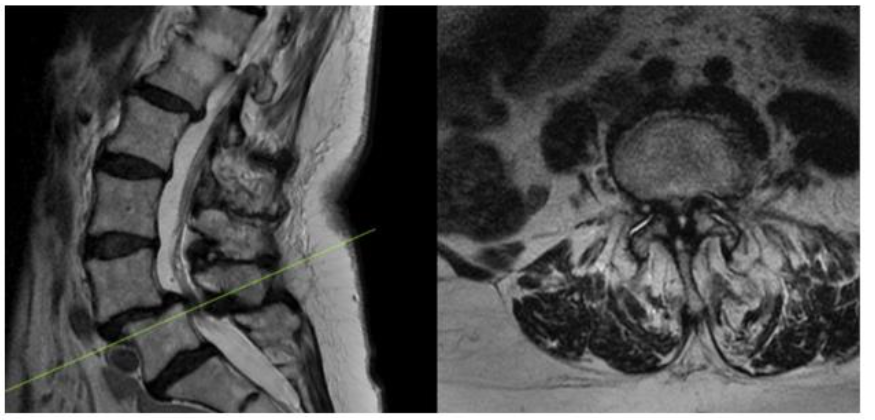

As part of an FDA approved device investigation study (NCT03115983) with Western IRB approval, between March 2016 and June 2020 all patients undergoing MI-TLIF with a single surgeon at our institution were prospectively reviewed to determine compliance with study parameters. Inclusion criteria included the presence of at least Grade 1 lumbar spondylolisthesis (per Meyerding classification) with associated spinal stenosis at one level between L1-S1 on either CT myelogram or MRI of the lumbar spine (Figure 1).

Figure 1. Preoperative MRI showing L4-5 Grade 1 Spondylolisthesis with associated stenosis